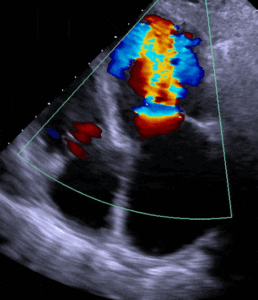

• Reconnaître les différentes structures et fonctionnements normaux du cœur en obtenant des vues échographiques de bases (identification des ventricules, valves et structure cardiaque, etc.).

• Réaliser des échographies, incluant les toutes les vues cardiaques nécessaires au diagnostic des pathologies les plus pertinentes.

• Identifier les pathologies les plus fréquentes en pratique clinique

• Partie 1 : Simulations avec une technologie de réalité virtuelle vise à obtenir une meilleure compréhension de la vision ultrasonographique et leur impact en temps réels sur les vues échographiques.

• Partie 2 : Simulation sur volontaire afin de pratiquer les échographies en contexte réel.

• Partie 3 : Simulation (détail de la technologie) pour diagnostiquer différentes pathologies cardiaques.